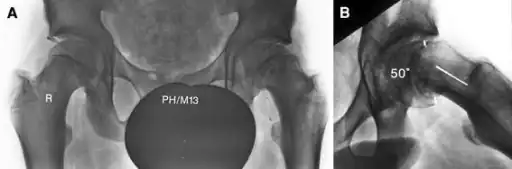

| X-ray showing a slipped capital femoral epiphysis, before and after surgical fixation. | |

The diagnosis requires x-rays of the pelvis, with anteriorposterior (AP) and frog-leg lateral views.[12] The appearance of the head of the femur in relation to the shaft likens that of a "melting ice cream cone", visible with Klein's line. The severity of the disease can be measured using the Southwick angle.